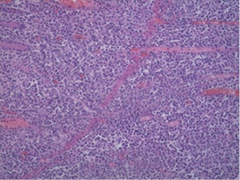

Contrast-enhanced Computerized Tomography (CECT) of the abdomen was the next diagnostics tool. The small intestine was presented with dilated loops, formed “air fluid levels” and free fluid in the Douglas pouch. The tumor formation itself was not detected by the radiologist on this scan (Figure 2).

Figure 2. CECT of abdomen with signs of small bowel obstruction